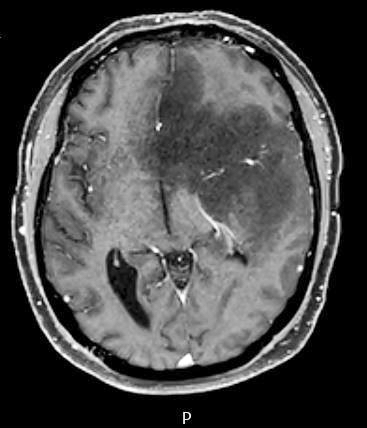

Radiology description

- CT:

- Expanding, intra-axial, poorly defined mass of low density

- Variable calcification may be seen

- Contrast enhancement and central hypodensity due to necrosis, occur with higher grades

- MRI:

- T1 hypodensity and T2 hyperintensity

- T2 hyperintensity with relative FLAIR sequence hypointensity (T2 FLAIR mismatch) is a relatively suggestive indication of IDH mutant astrocytoma (Clin Cancer Res 2017;23:6078)

- Distortion and enlargement of involved areas, including associated cortical ribbon

- Contrast enhancement is typically present in higher grade tumors (J Neurooncol 2019;141:327)

- Ring-like enhancement around central necrosis typical of grade 4

Radiology images